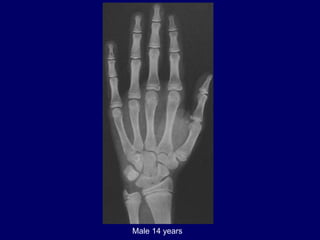

Male 14 years